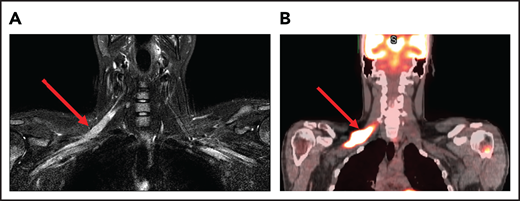

A 74-year-old man with a history of DLBCL treated with R-CHOP presented with progressive confusion and right-side weakness. A brain MRI demonstrated a contrast-enhancing lesion in the corpus callosum with extension into the left parietal region. A biopsy of the enhancing lesion confirmed a diagnosis of DLBCL. No other sites of disease were identified, and he was diagnosed with isolated CNS relapse. He was treated with HD-MTX, rituximab, and temozolomide for 4 cycles, and he achieved a complete radiographic response. Three years later, he presented with progressive memory loss, urinary incontinence, and gait ataxia. A brain MRI demonstrated periventricular white matter T2/FLAIR hyperintensities (Figure 3). Evaluation for toxic and metabolic causes of his symptoms was negative. His diagnosis was MTX-induced leukoencephalopathy.

Brain MRI of a patient with leukoencephalopathy caused by use of HD-MTX. An axial T2 fluid attenuated inversion recovery (FLAIR) image shows periventricular hyperintense signal reflecting leukoencephalopathy.

HD-MTX as well as IT MTX can cause acute as well as subacute encephalopathy.57,58 Acute encephalopathy is usually reversible. Subacute, or chronic, encephalopathy, as seen in case 4, is typically progressive, irreversible, and associated with high morbidity and mortality. It is a diagnosis of exclusion and as described in case 4, other causes must be excluded. The risk is higher with older age and when combined with whole-brain radiation therapy (WBRT).59